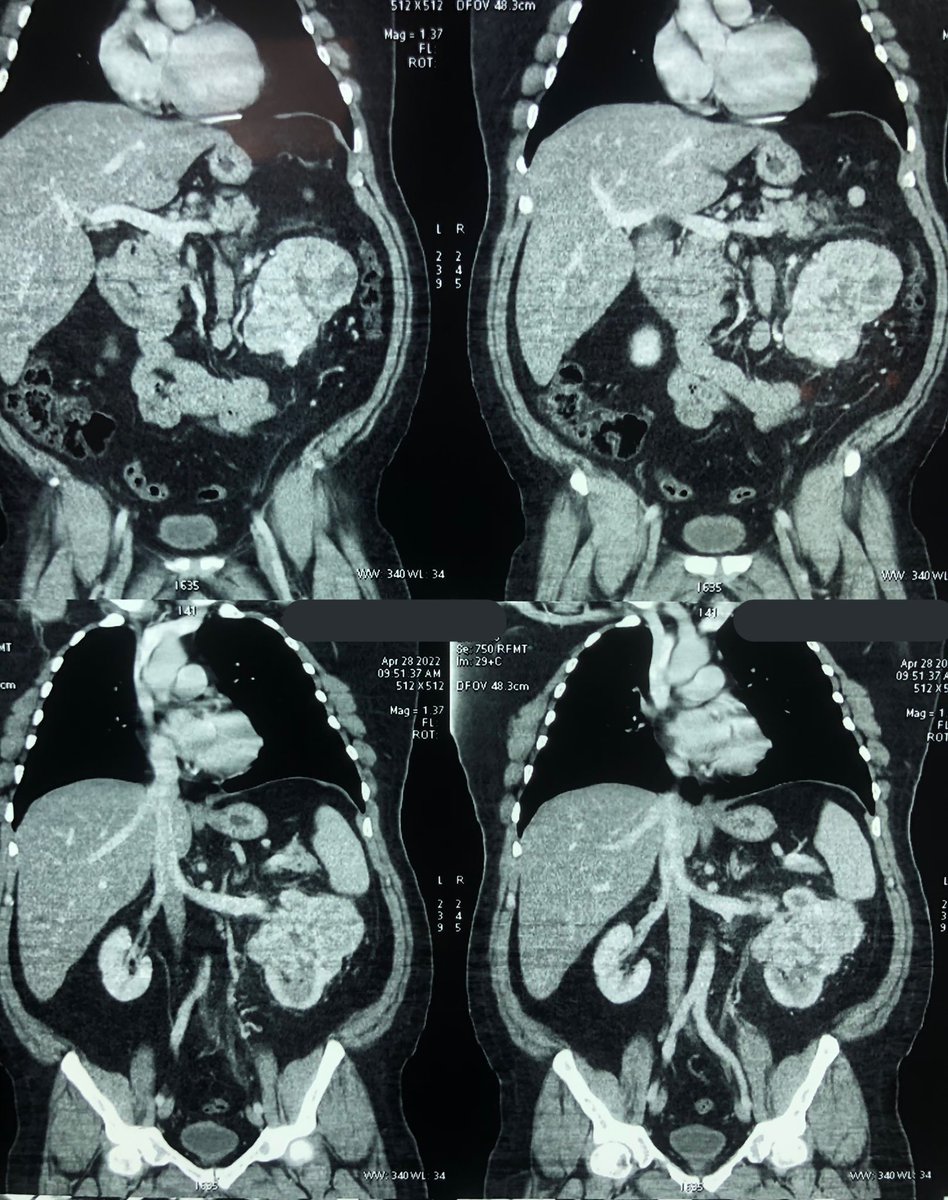

#CáncerdeRiñón Cirugía laparoscópica para retirar un tumor de riñón cuyo peso fue mayor a los 1200 gramos. Los factores de riesgo para esta enfermedad son: tabaquismo, hipertensión arterial y obesidad, entre otros. Gracias a los pacientes y familiares por su confianza

#CáncerdeRiñón

Cirugía laparoscópica para retirar un tumor de riñón cuyo peso fue mayor a los 1200 gramos.

Los factores de riesgo para esta enfermedad son: tabaquismo, hipertensión arterial y obesidad, entre otros.

Gracias a los pacientes y familiares por su confianza